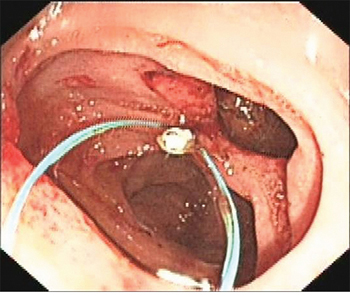

An Olympus double-lumen endoscope (Olympus, Center Valley, PA, USA) was used to attempt repair; however, the diameter of the injury was too long. A titanium clip was used to attempt closure of the perforation, but this technique failed. Therefore, an endoscopic purse-string suture was employed. First, the double-lumen endoscope was used to observe the location, size, and appearance of the injury. Then, the following steps were taken: (1) a nylon ring and a titanium clip were inserted along the double channels of the endoscope; (2) after adjusting the angle and location of the nylon ring and titanium clip, the first titanium clip was used to hold the distal end of the nylon ring vertically, firmly approximating the normal mucosa at the distal edge of the defect, and fixing it by deploying the clip (Figure 3); (3) several titanium clips were placed along the nylon string, around the perforation; (4) the last clip was inserted to hold the proximal end of the nylon ring, approximating and fixing it to the normal mucosa at the proximal edge of the defect; and (5) the nylon ring was retracted to draw the distal and proximal edges of the mucosa of the wound together. Endoscopy demonstrated that the perforation had been successfully closed (Figure 4). Postoperatively, a jejunal feeding tube and gastrointestinal decompression tube were placed; she was maintained on bowel rest and placed on antibiotics. Two days later, her abdominal pain was relieved, her abdominal tenderness was significantly reduced, and no rebound tenderness was demonstrated on examination. Subcutaneous emphysema was absorbed after 5 days. Enteral nutrition was initiated 5 days postoperatively. As there was no free intraperitoneal air on plain radiographs 10 days postoperatively, the gastrointestinal decompression tube was removed. After 3 weeks, the jejunal feeding tube was removed and the patient was discharged. At her 2-month follow-up visit, she had no complaints or symptoms.

Figure 3: Nylon string and first titanium clip.